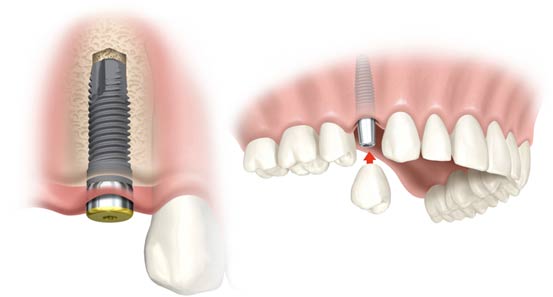

COS'E' UN IMPIANTO?

Un impianto è un corpo artificiale che viene inserito in un organismo vivente.

Gli impianti da noi utilizzati sono a forma di vite, hanno un diametro da 3,5 a 6,0 mm e una lunghezza da 5 a 15 mm, approssimativamente, quindi, la dimensione di una radice naturale.